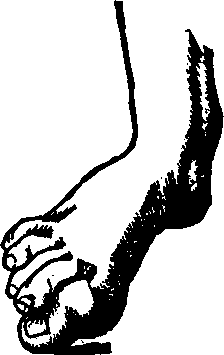

Fig. 3. THE UTERINE DILATOR. This instrument is introduced

into the canal of the uterine neck with its blades closed. By means of the

thumb-screw the blades are then separated as shown in this illustration,

the cervical canal being thereby dilated to the required extent.

Treatment. From the nature of this malady, it will readily be seen that no medical treatment can effect a radical cure. We must therefore resort to surgery. In a small proportion of cases, the stricture may be cured by repeated dilations of the constricted part of the cervical canal. This may be accomplished by using a very smooth probe which is fine at the point, but increases in size, so that its introduction will widen and expand the orifice and canal. The stricture may be overcome in many cases by using different sized probes. In some instances, we have employed the uterine dilator, represented by Fig. 3. We have also introduced sea-tangle and sponge tents into the neck of the womb, and allowed them to remain until they expanded by absorbing moisture from the surrounding tissues. The latter process is simple, and in many cases preferable. By means of a speculum (see Figs. 15 and 16), the mouth of the womb is brought into view, and the surgeon seizes a small tent with a pair of forceps and gently presses it into the neck of the womb, where it is left to expand and thus dilate the passage. If there seems to be a persistent disposition of the circular fibers of the cervix to contract, and thus close the canal, a surgical operation will be necessary to insure permanent relief. In performing this operation, we use a cutting instrument called the hysterotome (see Figs. 4 and 5). By the use of this instrument, the cervical canal is enlarged by an incision on either side. The operation is but slightly painful, and, in the hands of a competent surgeon, is perfectly safe. We have operated in a very large number of cases and have never known any alarming or dangerous symptoms to result. After the incision, a small roll of cotton, thoroughly saturated with glycerine, is applied to the incised parts, and a larger roll is introduced into the vagina. The second day after the operation, the cotton is removed, the edges of the wound separated by a uterine sound or probe, and a cotton tent introduced into the cervix, and allowed to remain, so that it will expand and thus open the wound to its full extent. This treatment must be thoroughly applied, and repeated every alternate day, until the incised parts are perfectly healed.